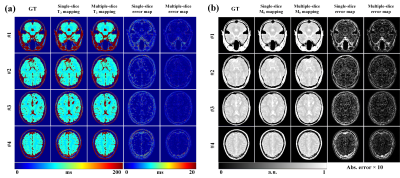

For intuitive assessment of the reconstruction results, Figure 3 shows four representative slices of one brain. We can see that the proposed method can achieve better reconstruction accuracy and higher image quality compared to single-slice method. Table 1 presents the averages and standard deviations of the root mean square error (RMSE) and structural similarity (SSIM) for the T2 and M0 maps. To further investigate the impacts of individual difference on the performance of the methods, the statistical values are summarized into box plots, as shown in Figure 4. It can be seen that the average performance of the proposed method is better than the single-slice method.

Figures 3. T2 mapping (a) and M0 mapping (b) results of four representative slices reconstructed using different methods.